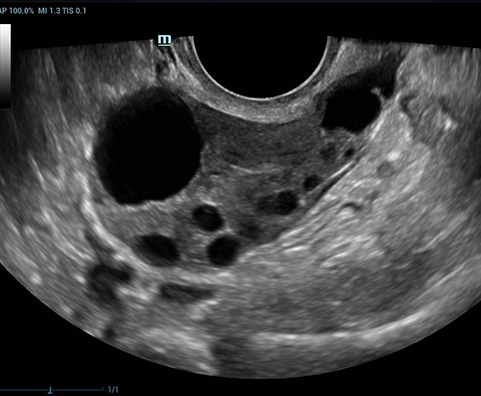

Desde su creaciÃģn, Mindray no ha dejado de explorar nuevas maneras de mejorar la fiabilidad del diagnÃģstico. Gracias a ZONE Sonography?, la tecnologÃa mÃĄs revolucionaria, la nueva plataforma ZST+ del Resona 7 eleva la calidad de imagen de ultrasonido mediante la adquisiciÃģn de zonas y el procesamiento de datos de canal.

AdemÃĄs de una calidad superior de la imagen, el Resona 7 tambiÃĐn mejora las capacidades de investigaciÃģn clÃnica gracias al revolucionario V Flow para la evaluaciÃģn hemodinÃĄmica vascular y la adquisiciÃģn de planos mÃĄs inteligente a partir de un conjunto de datos 3D para el diagnÃģstico CNS fetal. Combinando el funcionamiento multitÃĄctil mÃĄs intuitivo basado en gestos y todas las funciones clÃnicas esenciales, el Resona 7 estÃĄ realmente encabezando nuevas ondas en la innovaciÃģn del campo del ultrasonido.